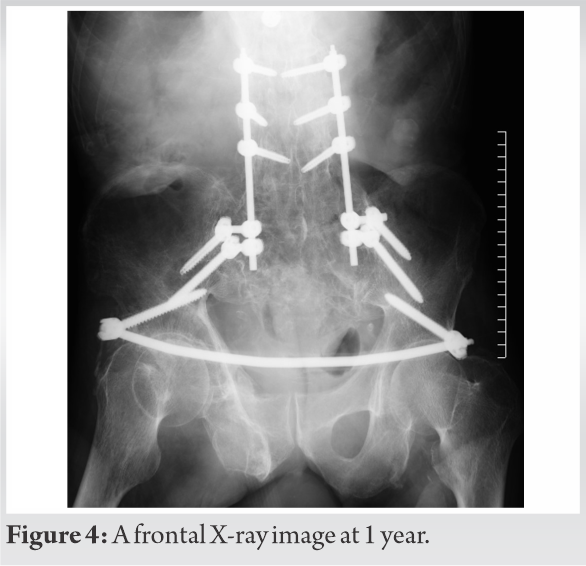

This patient also sustained a cerebral subarachnoid haemorrhage accompanied by a moderate consciousness disorder. Because of hypovolemic shock due to active bleeding from the common iliac arteries bilaterally, as detected on contrast-enhanced CT, and an unstable fracture, transcatheter arterial embolization, and external fixation of the pelvis were performed on the day of the injury (Fig. 2).